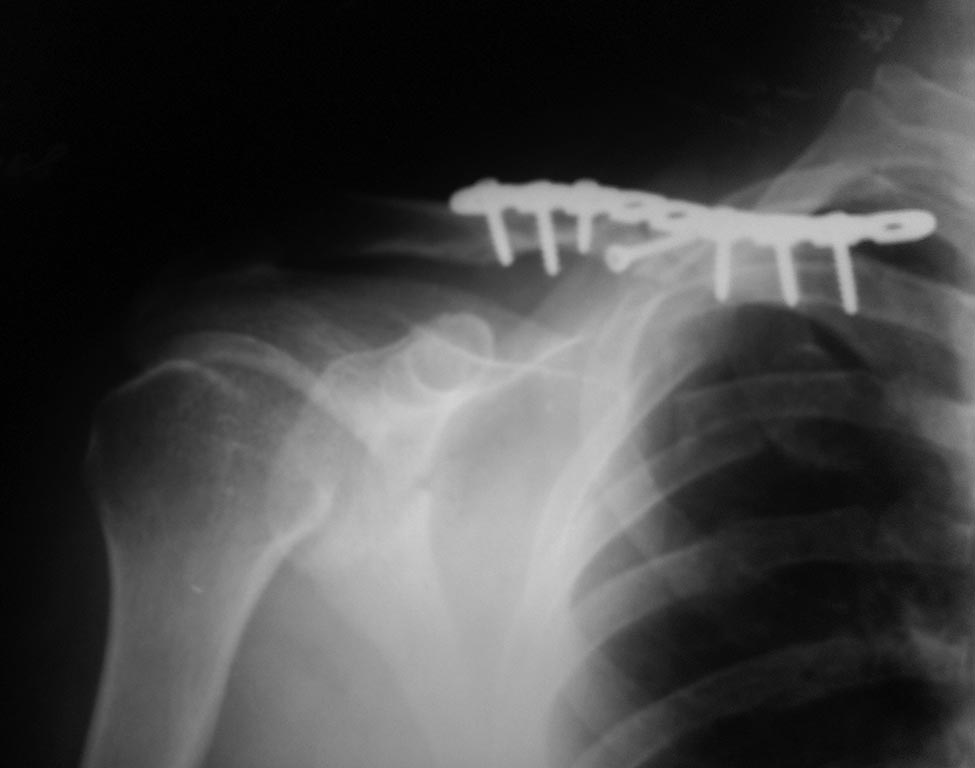

Пациент, 30 лет оперирован пластиной и винтами

Перелом на момент операции свежий, время операции - начало февраля 2015. Через 1,5 мес на контрольном снимке стояние пластины удовлетворительное.

Еще через месяц - диастаз дистального конца пластины и дистального отломка.

Важно: больной не соблюдал режим, через 2 недели от момента операции начал движения рукой.

Это несращение и несостоятельность фиксации. Рентгенологам надо объяснить, что они не правы.